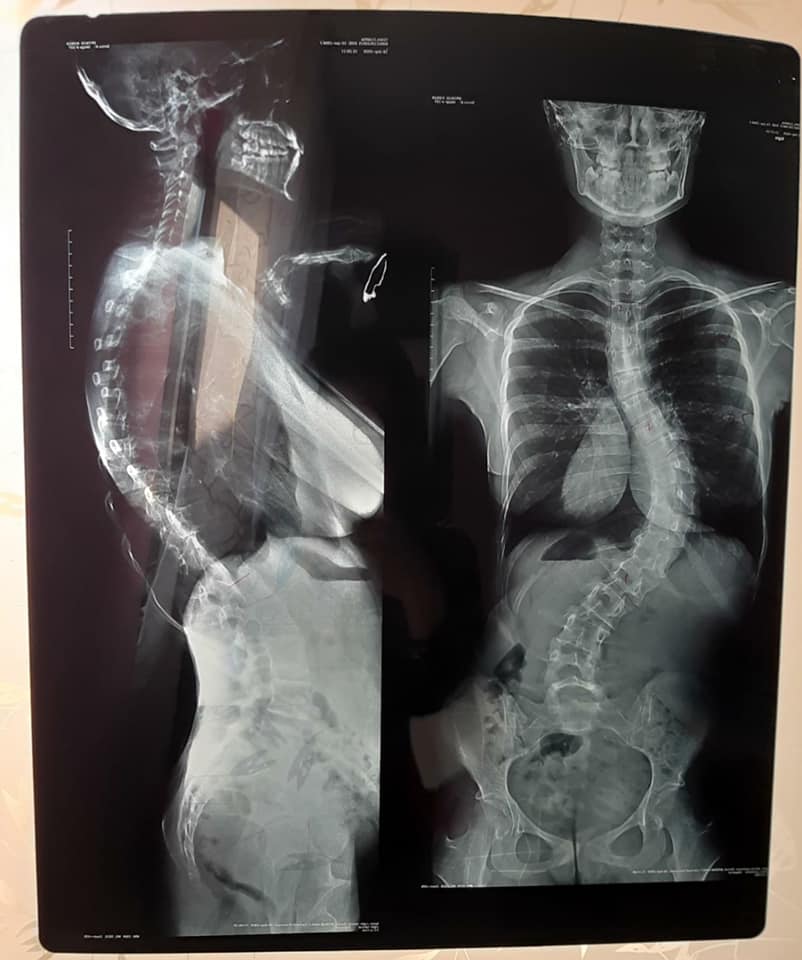

În urmă cu patru ani, Eleonora a fost diagnosticată cu scolioză toraco-lombară severă. Din păcate, cu timpul, starea ei s-a înrăutăţit, iar unghiul curbării coloanei sale a ajuns la 75 de grade. La doar 14 ani, Toma Clarisa Valentina Eleonora este în faţa unei încercări negre a vieţii, iar noi o putem ajuta!

În ultimii patru ani a încercat diferite metode de recuperare cum ar fi: kineto terapie, gimnastică recuperatorie, corsete medicale, însă niciunul dintre acestea nu a dat rezultatele dorite.

Apăsarea coloanei pe zona toracică (plămâni) i-a declanşat astmul, din cauza căruia nu mai poate să respire şi să trăiască o viaţă normală.